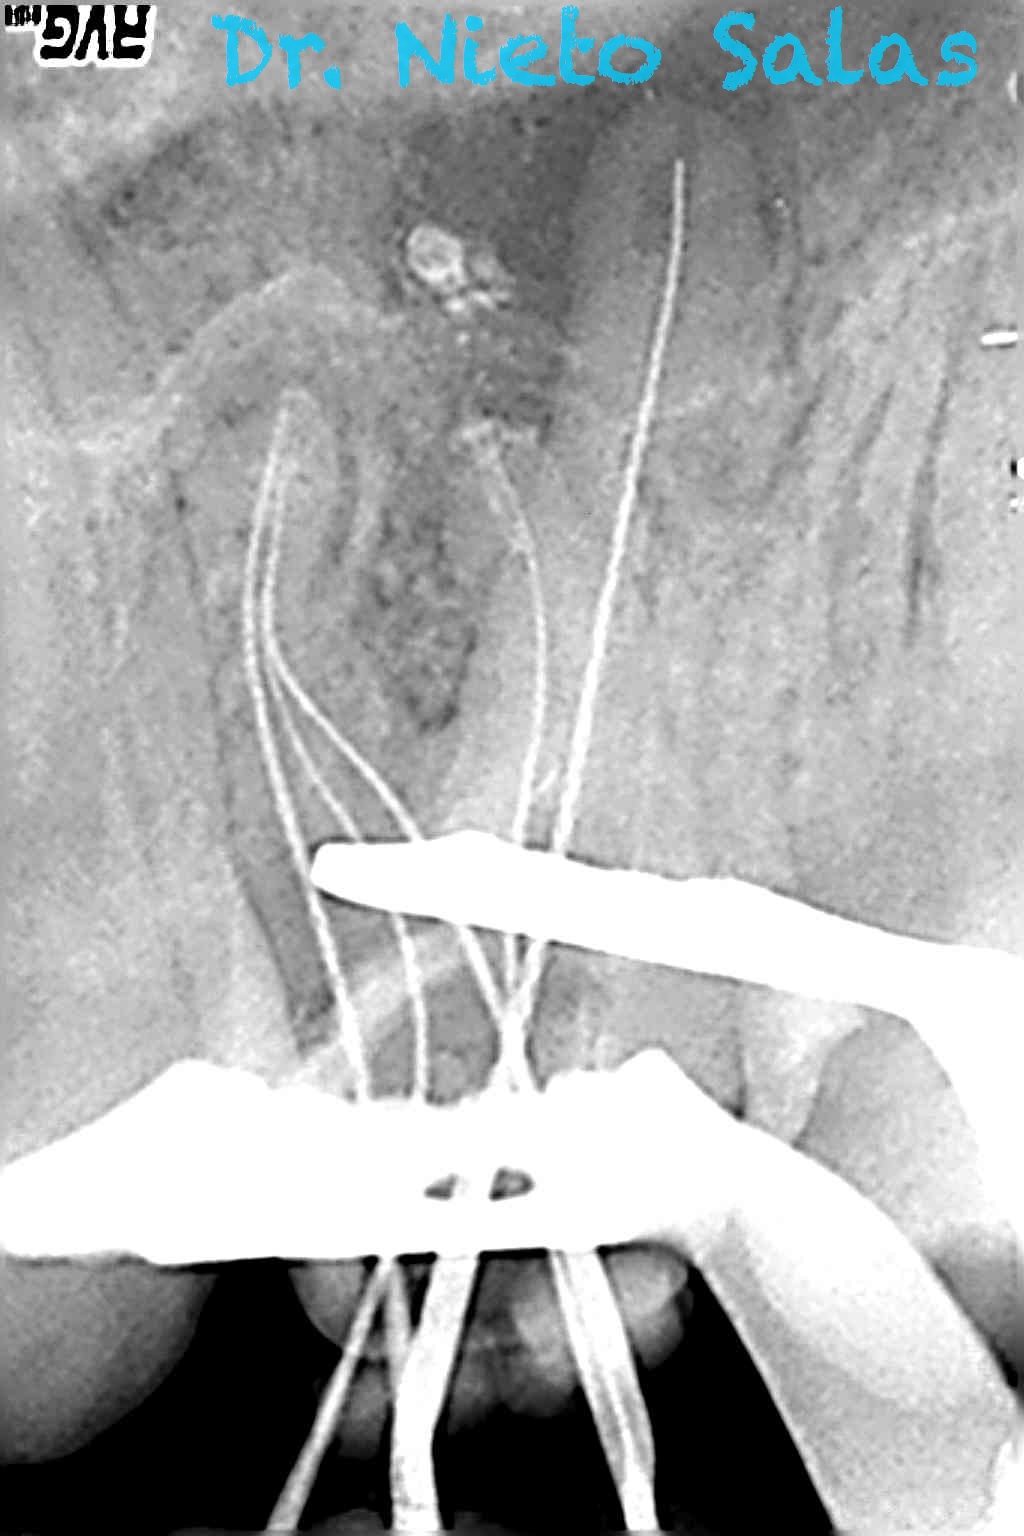

Os presento unos casos de varios molares superiores, con tres conductos mesiovestibulares con un foramen o con dos.

Una vez que tenemos medidas, obturamos los conductos: